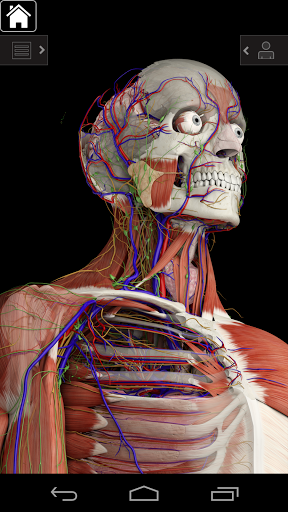

Основна анатомія 3 - це найновіша технологія та новаторський дизайн. Ріжучий 3D-графічний движок, зроблений на замовлення 3D4Medical з усього світу, наділений високоінформативною анатомічною моделлю і забезпечує високу якість графіки, яку не може досягти ніхто інший конкурент.

Програма являє собою унікальний підхід до вивчення загальної анатомії. Графіка не має аналогів і навчається, використовуючи інформативний контент та інноваційні функції, багатий та захоплюючий досвід.

Основна Анатомія 3 чутлива, візуально приголомшлива і легка. Додаток повністю 3D, що означає, що ви можете переглядати будь-яку анатомічну структуру окремо, а також з будь-якого кута.

Основна Анатомія 3 розроблена з урахуванням користувача - сам орган стає інтерфейсом. На відміну від інших 3D-додатків, які покладаються на попередньо визначені анатомічні механізми та регіональні розділи для керівництва користувача, 3D4Medical's Essential Anatomy 3 дозволяє знайти те, що ви шукаєте, без ускладнень.